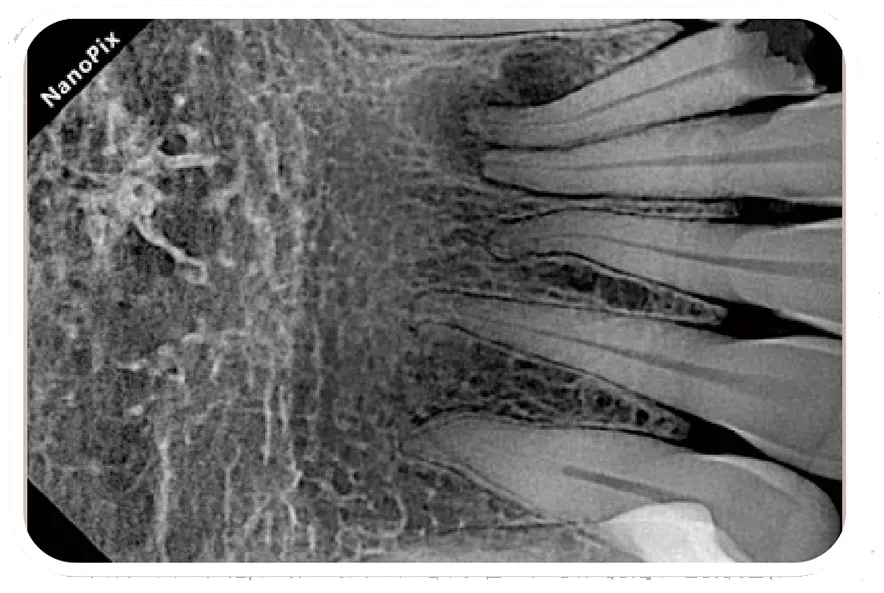

Клинические изображения

Чёткое изображение с высоким разрешением и фокальным пятном 0.4 мм